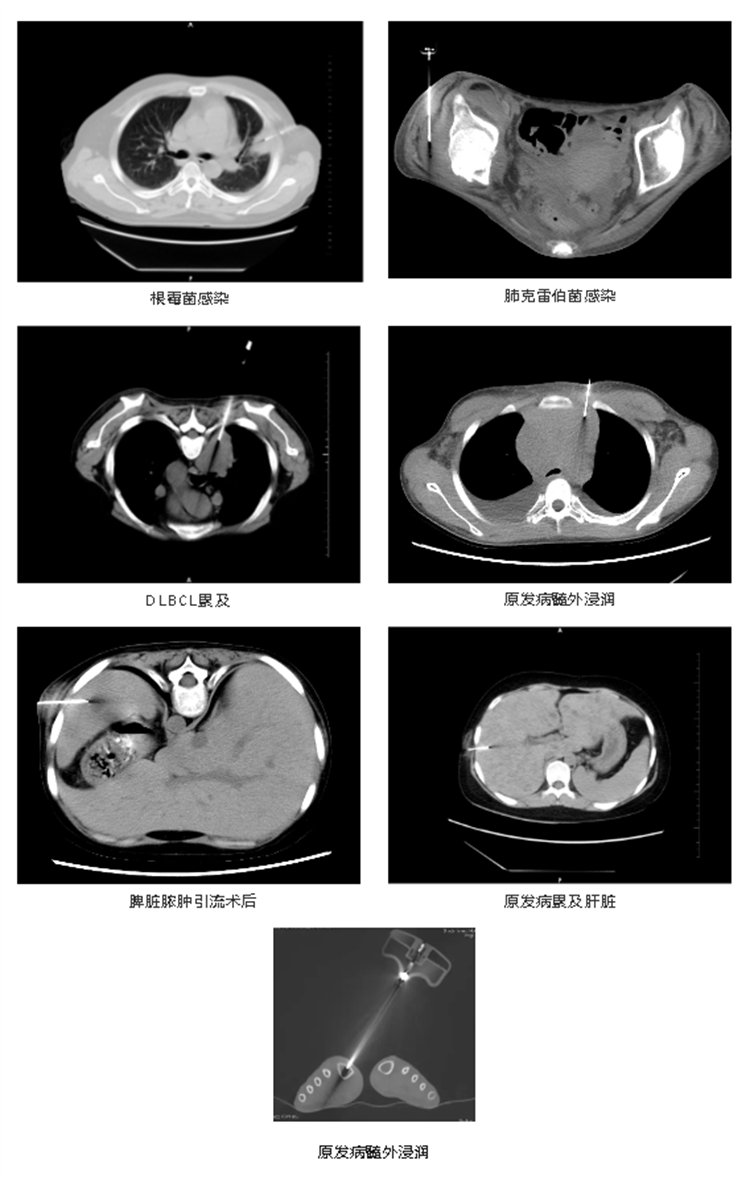

實(shí)際病例展示

657812bb507a7.png

657812c4e76c1.jpg

此項(xiàng)技術(shù)傷口創(chuàng)面小,對(duì)患者來說,經(jīng)濟(jì)適用,也可以為臨床治療和預(yù)后判斷提供更多的病理學(xué)信息和依據(jù)。